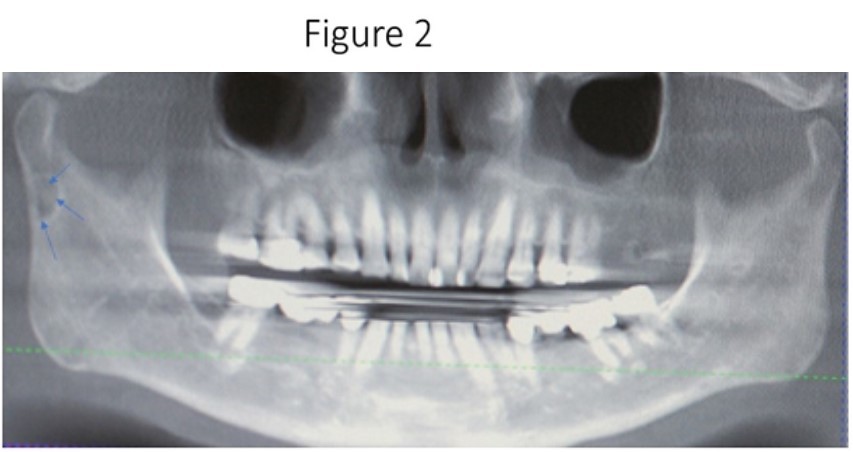

Maxillofacial examination was unremarkable. No facial swelling, masses or asymmetry was observed. The TMJ examination was normal. No pain or tenderness to digital palpation was observed in the right preauricular region. Oral examination of the patient was unremarkable. No trismus was observed as the maximal interincisive opening was greater than 40.0mm. No anterior or posterior open bite was observed. Imagining studies to rule-out intraosseous neoplastic lesions and arrive at a definitive diagnosis consisted of a panoramic radiograph and cone beam CT scan (120 kVp, 5 mA, 7.4 sec). Panoramic radiograph revealed a unilocular, well-circumscribed radiolucency in the right subcondyalar region of the mandible that was close to the posterior border of the condylar neck (Figure 2). Cone beam CT scan (i-CAT FLX, Imaging Sciences, Hatfield, PA) imaging revealed a well-defined unilocular, elliptical shaped radiolucent lesion on the medial surface of the right subcondylar neck of the mandible (Figure 3, Figure 4, Figure 5). The elliptical shaped unilocular lesion involved almost the entire horizontal dimension of the subcondylar neck (Figure 4). Figure 5 shows the three-dimensional CT scan reconstruction (i-CAT FLX, Imaging Sciences, Hatfield, PA) of the medial defect in the subcondylar region of the mandible. Based on knowledge of clinical head and neck anatomy and imaging studies, no treatment was indicated as the diagnosis was consistent with a variant of a Stafne bone cavity of the right subcondylar neck near the parotid gland and not a pathological condition. The patient was informed about the risk of condylar neck fracture due to the critical size of the SBC.

Figure 2.Panoramic radiograph reveals a unilocular radiolucency in the right subcondylar neck of the mandible which is considered a variant of the classic SBC described by Dr. Stafne.